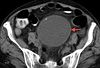

A 26-year-old man presented with sudden onset of palpitations and shortness of breath after incidentally taking tadalafil. He had no other symptoms and no history of illnesses during childhood. He drank socially but denied smoking and use of illicit drugs.